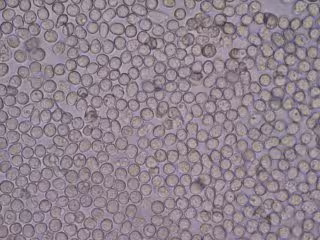

Glóbulos Blancos

Glóbulos Blancos - BOBJGALINDO/WIKIMEDIA COMMONS - Archivo